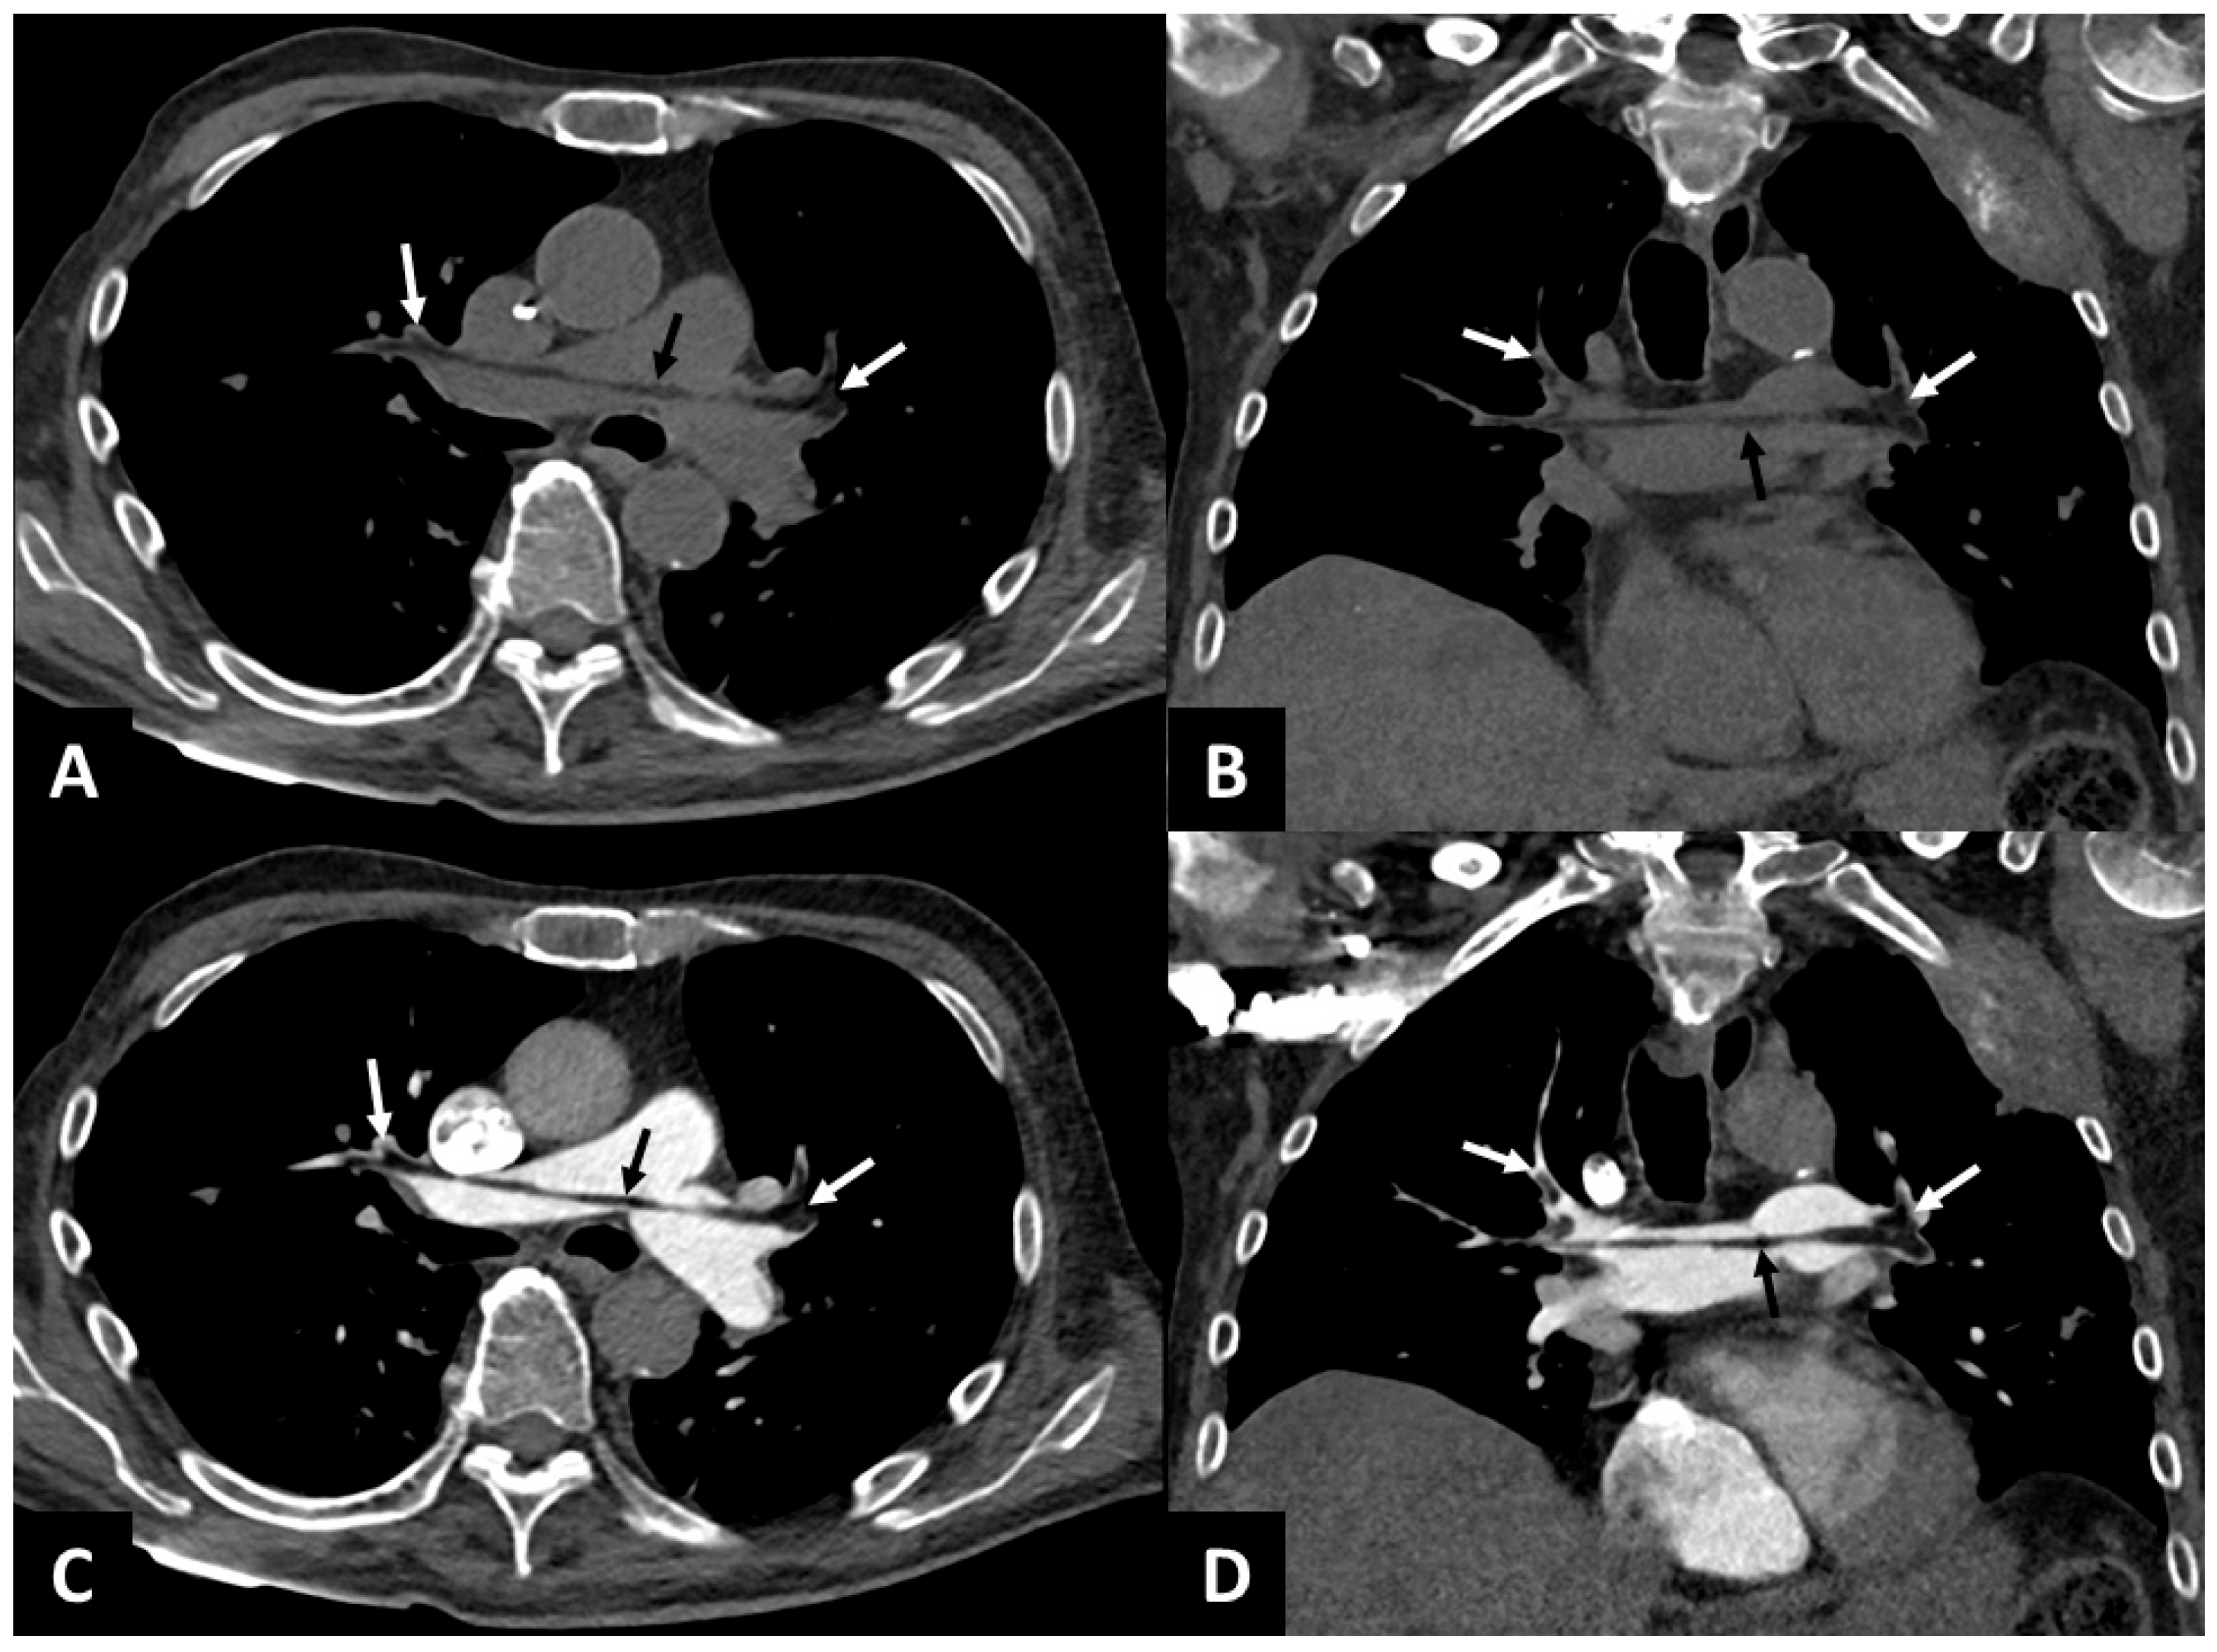

Proximal Pulmonary Fat Embolism on Non-Contrast Chest CT

L’Huillier, R.; Braillon, A. Proximal Pulmonary Fat Embolism on Non-Contrast Chest CT. Diagnostics 2025, 15, 2468. https://doi.org/10.3390/diagnostics15192468